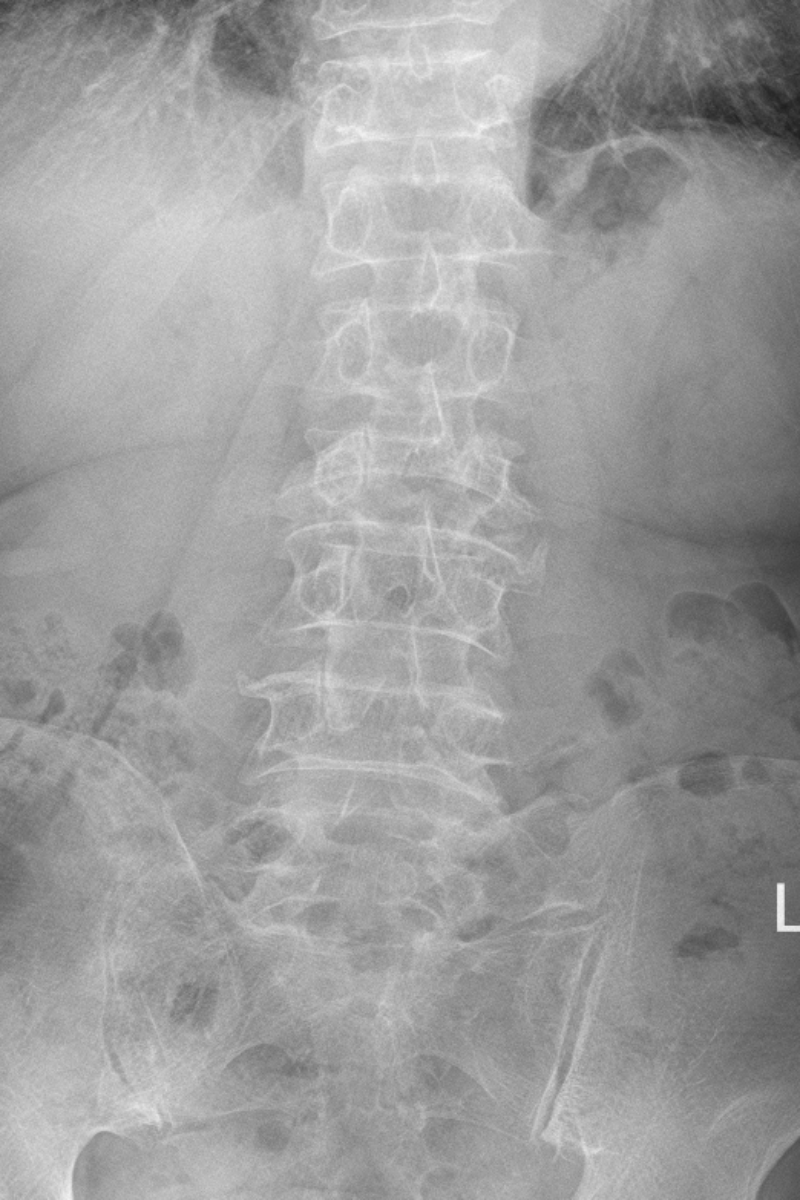

老年患者椎體骨折的微創手術治療

69歲的何阿婆,1個多月前無明顯誘因開始出現腰背部疼痛,起身活動時明顯,自己吃止痛藥、敷中藥后沒有明顯好轉,嚴重影響她的生活,張阿婆便到當地醫院就診,行腰椎MRI提示腰5椎體新鮮壓縮性骨折,便到我院脊柱外科住院治療。這種骨折往往發生在骨質疏松的老年人,這類病人如保守治療,需要絕對臥床休息2-3個月,嚴重影響生活質量,長期臥床還可能出現褥瘡、墜積性肺炎、深靜脈血栓等風險,甚至可能危及生命。何阿婆對手術非常恐懼和忐忑,姚仕奮團隊對何阿婆完善檢查,評估其身體可耐受手術,與何阿婆和她的家里人耐心溝通病情,告訴他們只需要在局部麻醉下做一個微創手術,傷口不需要縫針,做完手術第二天就可以下地行走了,張阿婆和她家里人對手術和保守治療的利弊完全了解后,決定接受手術治療。脊柱團隊在2023年11月15日對張阿婆施行了經皮腰5椎體成形術,術后第一天張阿婆在醫護人員的指導下,可以自己下地行走,并順利出院。

這類骨折患者以往到我院就診,大部分采取保守治療,有手術意愿的患者則需自行前往惠州市級醫院進行手術,在惠州市中心人民醫院醫聯體平臺下,優質資源下沉,我院已可常規行椎體成形手術治療,脊柱外科開科一個月來,已完成椎體成形術15臺次,今后將以更專業的醫療技術為群眾服務。